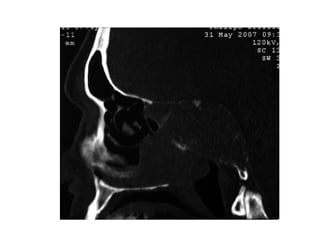

Fracture des os propres du nez : radioFracture des os propres du nez : radio

des OPNdes OPN